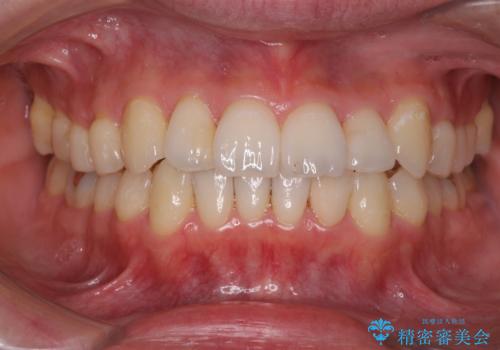

プラスチックの詰め物と比較して、変色もなく、脱離もしにくいセラミッククラウンで修復しました。

前歯のステインはエアフローという方法で綺麗にクリーニングしています。

- 16.5万円(仮歯1.1万円、セラミッククラウン(ジルコニアクラウン・スペシャル)15.4万円) エアフロー代別(1時間/1.1万円)費用は治療当時の料金となります

矯正治療前のかみ合わせのせいでかなり削れてしまっていたようです。その場合、矯正治療後に修復するのがおすすめです。

また、クラウンに修復するメリットとして、そのまま使っていると欠けているせいで薄い歯質がうすくなり、さらに割れてしまうリスクを防止することができます。